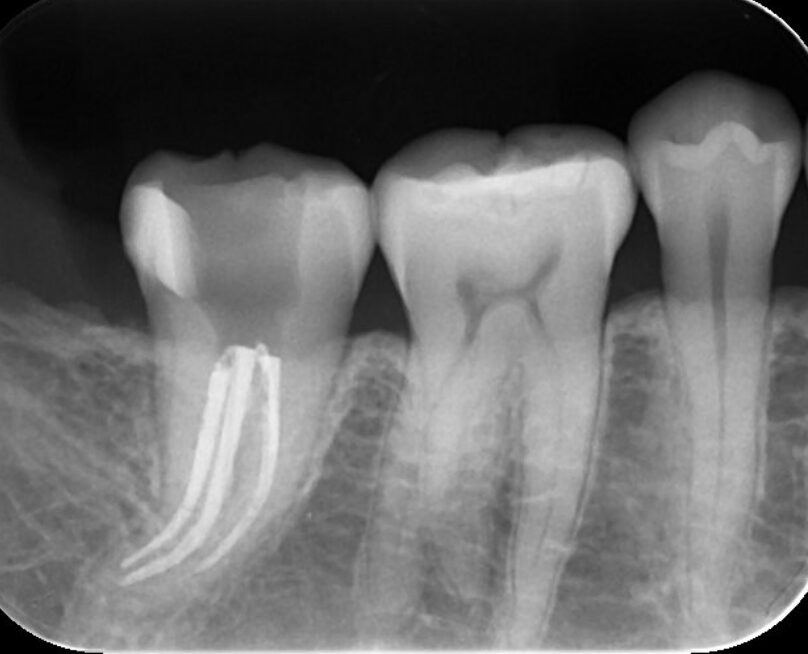

根管治療後のデンタルX戦写真